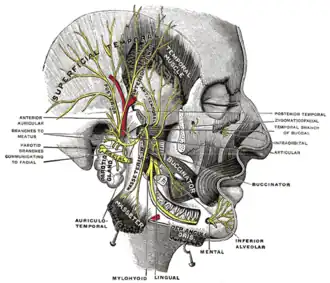

Mandibular division of the trifacial nerve.

Mandibular division of the trifacial nerve. -